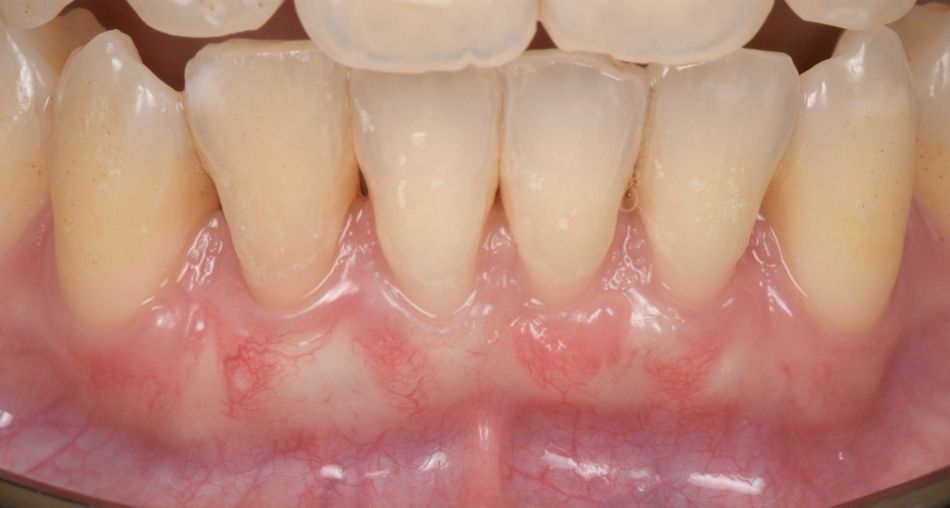

A 35-year-old female, healthy (ASA I), non-smoker, with no medication, came to our practice complaining about gingival recession and pain while brushing her mandibular incisors.

The intraoral examination revealed multiple RT 1 (Cairo 2011) gingival recessions on teeth #33 to #43, along with a thin tissue phenotype, which was associated with a traumatic toothbrushing habit (Fig. 1).